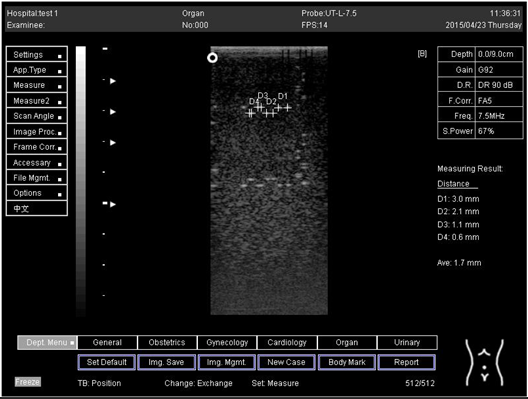

9.0 Axial resolution

Biomimetics 07 00130 i001

D1 = 4.9

D2 = 4.1

D3 = 3.1

D4 = 2.2

Lateral resolution

Biomimetics 07 00130 i002

D1 = 5.0

D2 = 4.0

D3 = 3.0